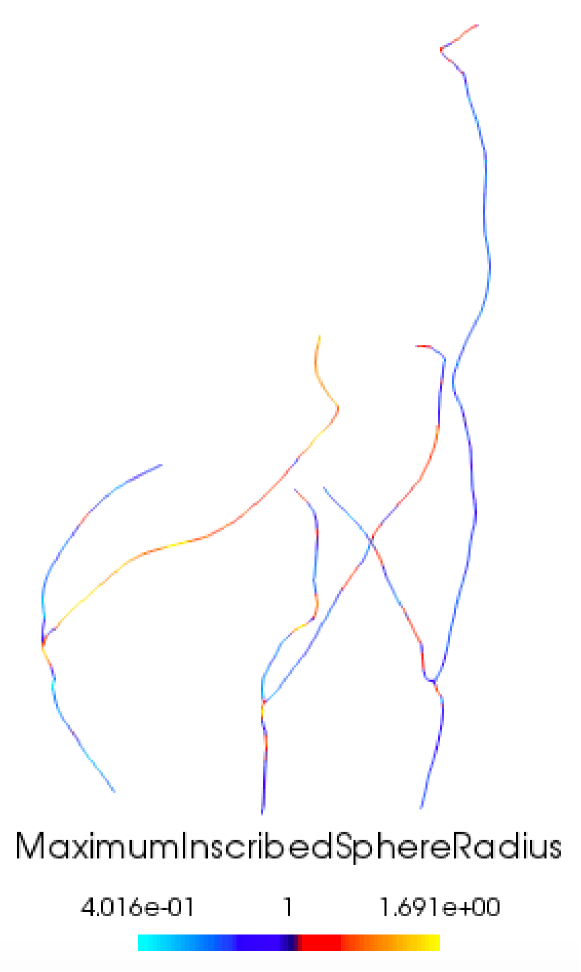

To generate sufficiently smooth surfaces preserving the same anatomical structures as reconstructed surfaces, we follow a centerlines-based approach (Ballarin et al., 2016, 2017). We extract centerlines, that are the lines between two sections of lumen such that their minimal distance from the boundary is maximal (Antiga et al., 2008, Piccinelli et al., 2009, Ballarin et al., 2017) using VMTK, which also outputs maximum inscribed spheres radii values associated to each point on the centerlines. After running average smoothing, we insert polyballs around the points on the centerlines according to the associated maximum inscribed spheres radii values. This yield a smooth 3D volume preserving patient-specific anatomical configuration (Ballarin et al., 2016, 2017). The algorithm is summarized in figure 2.